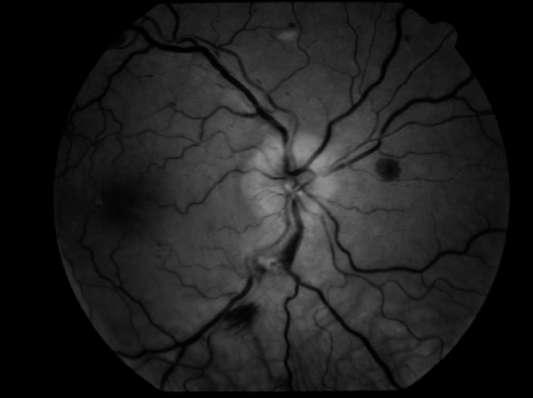

Caso aportado por Dr. Tomás Gonzáles y Nathan Dukes

ü Hombre 19 años portador de Leucemia linfatica aguda diagnosticada el 2016, es tratado ese mismo año con trasplante alogénico, sin embargo 4 meses posterior al trasplante sufre una recaída leucémica. Desde entonces el paciente se ha mantenido en QMT sistémica paliativa

ü El año 2017 el paciente evoluciona con enfermedad injerto contra huesped y el 2018 con meningitis leucémica

ü El año 2019 consulta en el policlínico de oftalmología del Hospital del Salvador por disminución de AV ODI de 7 dias evolución, asociado a sensación de cuerpo extraño.

Examen Físico

ü AV con CAE: 20/70 OD y 20/60 OI

ü PIO normal bilateral

ü DPAR en OD

ü Motilidad ocular conservada.

ü BMC: Puntata extensa como consecuencia de efectos adversos producidos por la QMT (Imagen A y B) A